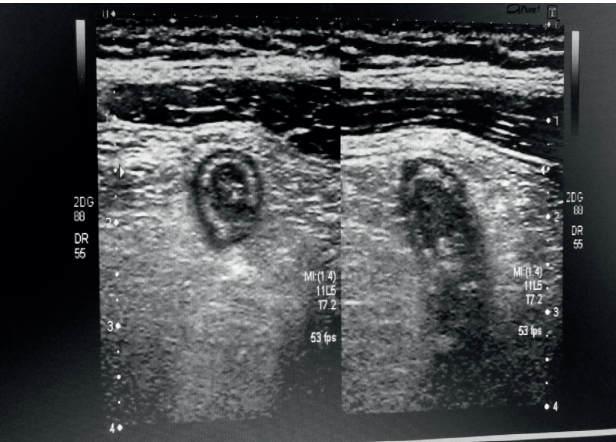

A respeito da imagem acima e tendo em visto as características de intussuscepção intestinal, assinale a alternativa incorreta.

Com base na imagem acima, assinale a alternativa que apresenta achado ultrassonográfico compatível com apendicite aguda.